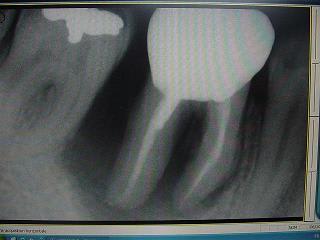

ci joint des retro de mars 2001 et aout 2003 de 46 qui montre l'evolution du cas..

bon, je suis loin d'etre d'acc avec vous consernant l'endo: regardez l'evolution de la lesion, de 2001 à 2003, sur les retro: il me semble très peu probable que l'endo ( pas top, ok mais d'apparence pas si tocarde) soit en cause. On voit en 2001 une atteinte distale, clairement paro.

En plus, problème endo sur 46, sur 35 et 17 qui engendrerais de telles lésion, c'est twilight zone! pour l'occlusion, je suis plus d'accord dans son role agravant important.

Pour revenir à une eventuelle origine endo, quelqu'un a déja vu une telle atteinte endo? ( je doute...)